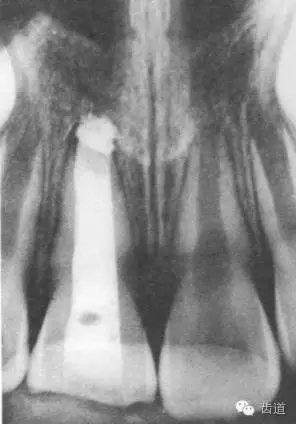

術(shù)后一個(gè)月

術(shù)后當(dāng)天

術(shù)后11個(gè)月

術(shù)后五個(gè)月